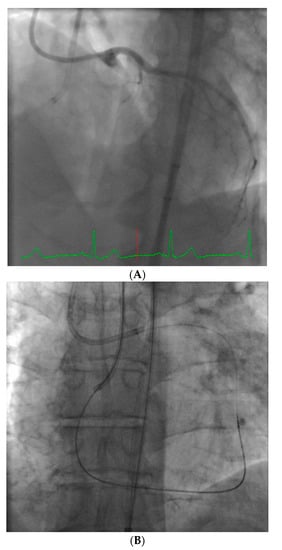

Figure 5.

These images are from a 52 year-old with angina and a chronic total occlusion of the LAD (A). The lesion was crossed successfully using retrograde techniques from the RCA; this step was performed manually (B). After the retrograde wire was externalized, the procedure was converted to robotic assistance and subsequent balloon, stenting, and post-stent balloon dilatations were performed with the operator in the cockpit, thus reducing radiation exposure by 50% (C). The final result is shown in (D).